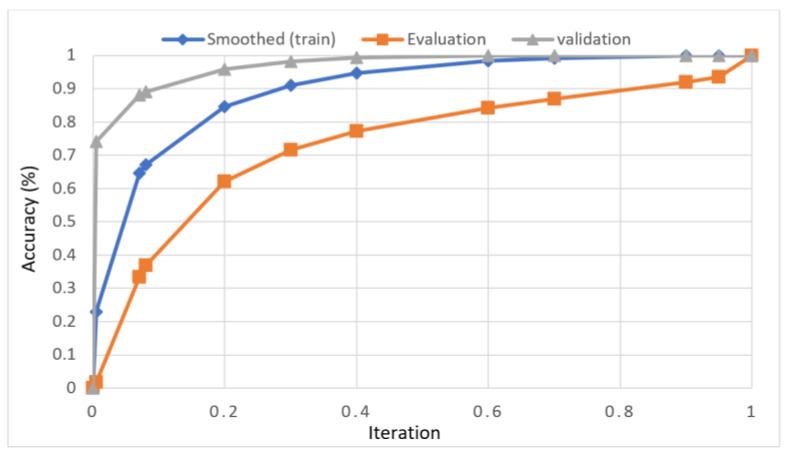

For knee RA severity classification, we conducted this research using a modified version of the VGG16 architecture and a domain adaptation technique, as shown in Figure 3. The VGG16 model was made up of five convolutional layers, three max-pooling layers, and three fully connected layers—all the digital X-radiation images needed to be resized to (227 × 227 × 3). In our implementation, X-radiation image information for training purposes accounted for eighty percent of the total, while X-radiation image information for evaluating purposes accounted for twenty percent. Although there are sixteen layers in VGG16, only a subset of those layers is required for feature extraction. In order to shorten the amount of time needed for training and establish more control over the fitting process, we assigned a dropout ratio value of 0.5 to the completely connected layer (fcl6) and the fully connected layer (fcl7). The characteristics were taken from the fully connected layers designated fcl6 and fcl7, respectively. To categorize the retrieved features into 1000 categories, VGG16’s architecture used a fully connected layer (fcl8). Then, we conducted one last round of tuning on the pre-trained VGG16 model’s ability to classify RA by changing parameters in the model’s last three layers. The model’s last three layers were swapped out for a fully linked layer, a softmax layer, and a classification layer. In addition, a newly linked layer was assigned to five groups of RA grades for the dataset: Grade 0, Grade 1, Grade 2, Grade 3, and Grade 4. We trained the proposed network by using digital knee X-radiations, a small-batch test dataset, gradient descent, and maximal epochs. Our proposed network learning strategy used stochastic gradient descent, and we compared its performance to previous efforts. The proportion of knee X-radiation images from the test set for which the network correctly predicted the RA grade was used to calculate proposed work accuracy. The proposed approach achieved an overall accuracy of 99.10% in classifying knee RA cases. Table 5 illustrates the Visual Geometry Group (VGG16) CNN operation for RA grade classification. Figure 4, depicts the RA classification using VGG16 architecture.

Sample images of the marginal joint space narrowing region of interest can be seen in Figure 5. The IoU (Intersection of Union) metrics were used to evaluate our region of interest detection system. This metric was the size of the intersection between the area of the actual bounding box and the area of the predicted bounding box divided by the size of the area of both boxes added together. When the IoU was 0.70, the narrow marginal joint space was found in 99.72% of the knee joints using our presented model. Additionally, Figure 6 depicts the ROC curve for marginal joint space narrow detection. The results of the presented marginal joint space narrow detection model obtained a sensitivity rate of 98.67%, a Dice score of 98.58%, a precision rate of 98.46%, a specificity rate of 98.50%, a false positive rate of 0.0100, a false negative rate of 0.0197, and an overall accuracy rate of 98.97%, as shown in Table 6, and the graphical illustration of Table 6 values is depicted in Figure 7. Table 7 demonstrates the metric performance outcomes of the proposed ResNet101 and VGG16 model to classify the RA. From Table 7, the outcome of the VGG16 outperforms the well-pre-trained ResNet101 model in classifying RA.

The presented model achieved 99.10% accuracy on the whole test set. The confusion matrix of the presented method is shown in Figure 8, and its performance is compared in detail to that of current methods in Table 5. In Figure 8, we examine the training and learning procedure as a whole to assess the planned activity’s success. Table 6 demonstrates the highest accuracy rate for classifying CBD grades zero–three–four knee joints. The knee joints with a CBD grade of one or two are the toughest to categorize. As can be seen in Figure 8, there is only a marginal amount of room for error when classifying knee joints as CBD Grades zero, three, or four. Knee joints that are classified as CBD Grades one or two have a small number of marginal misclassifications. In several circumstances, the proposed approach incorrectly estimated CBD Grade two as Grade one and vice versa. Joint space narrowing and bony spur development are significantly different in CBD Grade four knee joints. However, CBD-grade one knee joints show little change in JSN or osteophyte growth compared with the other classes. Types of knee RA and their intensity levels are shown in Figure 5. Table 8 and Figure 9 illustrate the JSN accuracy of the proposed and other state-of-the-art methods comparison.

In this study, we developed a deep learning model to automatically grade the severity of knee RA using a consensus-based approach. We compared the proposed work to prior strategies and found that it outperformed the competition. At the elementary level, notably in Grade one and Grade two, we found that our method differed from that of the medical professionals. We evaluated the presented work by comparing its results with similar existing studies. Compared with previously existing models, the presented work (a knee joint space narrowing diagnosis and class label) fares very well. It takes about 7 h of training to reach 0.6 k iterations. The outcomes of the presented methodology are shown in Table 9, which includes the outcomes of each CBD grade individually. Multiple metrics were employed to estimate the model’s performance, as indicated in Table 10. Figure 10 and Figure 11 depict the ROI curve for RA severity classification for both knees.